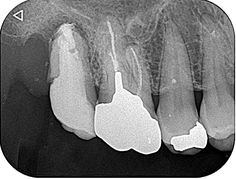

デンタル上で17根尖部から遠心にかけて透過像を認めました。歯冠遠心部はう蝕で崩壊しており、一見すると保存不可能に見える状態です。補綴物を撤去し、軟化象牙質を慎重に除去したところ、近心には十分な健全歯質が残存し、遠心にも健全歯質を保存することができました。レントゲンはあくまで画像であり、実際の状態と相違がある場合があります。レントゲンだけで判断する危険性を、改めて実感しました。

8か月後の経過観察になります。根尖部の透過像は大幅に縮小していることが確認できます。患者さんの自覚症状もなく、良好に経過しております。抜歯しなくて大丈夫だったことを大変喜ばれておりました。